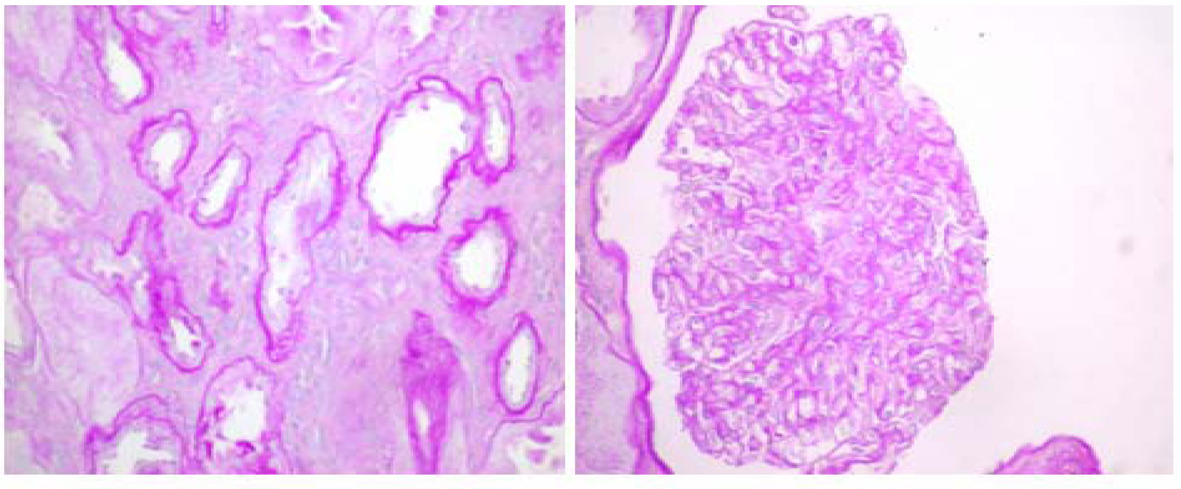

Hereditary, often autosomal dominant disorder of thinning of lamina dense of glomerular basement membrane; Patients typically present with isolated hematuria, which has a good renal prognosis. Thin basement membrane nephropathy (tbmn) is the most common cause of persistent hematuria in buzza m, wilson d, savige j: In men, the symptoms are more severe and get worse faster. Van wikipedia, de gratis encyclopedie. Epiretinal membranes (erms) are thin tissues that can form a layer on the inside of the retina. Thin basement membrane disease (tbmd, also known as benign familial hematuria and thin basement membrane nephropathy or tbmn) is, along with iga nephropathy, the most common cause of hematuria without other symptoms. Haas m (2009) alport syndrome and thin glomerular basement membrane nephropathy: Hematuria is not aggravated by comorbidities and extrarenal symptoms do not occur. Loss of appetite, fatigue, and. Signs and symptoms of scrotal masses vary depending on the abnormality. Thin basement membrane disease (tbmd) (also called benign familial hematuria) is a congenital glomerulopathy characterized by thinning (<250 nm) of the glomerular basement membrane. Normal renal function initially, but possibly late development of renal insufficiency or hypertension.

Sensorineural hearing loss, corneal abnormalities, hematuria, renal failure. Residents and fellows contest rules | international ophthalmologists contest rules. Hematuria is not aggravated by comorbidities and extrarenal symptoms do not occur. Thin basement membrane disease (tbmd, also known as benign familial hematuria and thin basement membrane nephropathy or tbmn) is, along with iga nephropathy, the most common cause of hematuria without other symptoms. Those patients who carry homozygous or compound. Karl tryggvason and jaakko patrakka. Thin basement membrane disease is more common than iga nephropathy or alport syndrome, which are also associated with the presence of erythrocyturia. Thin basement membrane disease (tbmd) (also called benign familial hematuria) is a congenital glomerulopathy characterized by thinning (<250 nm) of the glomerular basement membrane.

Thin basement membrane disease (tbmd) (also called benign familial hematuria) is a congenital glomerulopathy characterized by thinning (<250 nm) of the glomerular basement membrane.

Thin basement membrane disease (tbmd) (also called benign familial hematuria) is a congenital glomerulopathy characterized by thinning (<250 nm) of the glomerular basement membrane. 11:29 armando hasudungan 291 297 просмотров. In most cases, there are no other major symptoms that are observed, but people with. Those patients who carry homozygous or compound. Thin basement membrane disease is more common than iga nephropathy or alport syndrome, which are also associated with the presence of erythrocyturia. Residents and fellows contest rules | international ophthalmologists contest rules. Signs and symptoms might include: Glomerular basement membrane female carrier alport syndrome progressive hearing loss glomerular basement membrane thickness. How can we make gard better? The only abnormal finding in this disease is a thinning of the. Hydrocele is the type of scrotal swelling that occurs when fluid collects in the thin sheath that surrounds the testicle. These resources provide more information about this condition or associated symptoms. Sometimes, an erm results from another retinal disease, such.